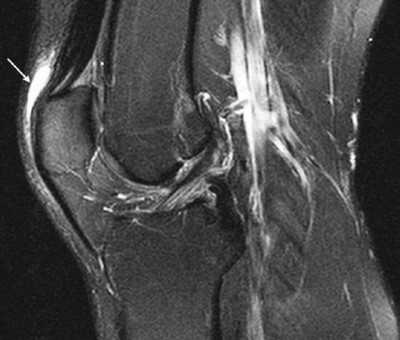

Препателлярный бурсит

Воспаление передней подкожной преднадколенниковой сумки на МРТ (стрелка)

Препателлярная бурса представляет собой трехкомпонентную структуру. Поверхностный отсек находится между подкожной клетчаткой и продолжением широкой фасции бедра, средний - между поперечной поверхностной и промежуточной косой фасциями. Глубокий ограничен косой соединительнотканной оболочкой и продольными волокнами сухожилия прямой мышцы бедра. Воспаление указанной синовиальной сумки происходит от длительного стояния на коленях, патологию регистрируют при подагре. Основные клинические проявления - боль и припухлость. Хроническая травматизация приводит к воспалению и геморрагическому бурситу. На МРТ препателлярный бурсит проявляется в виде овального жидкостного образования между подкожной клетчаткой и надколенником.